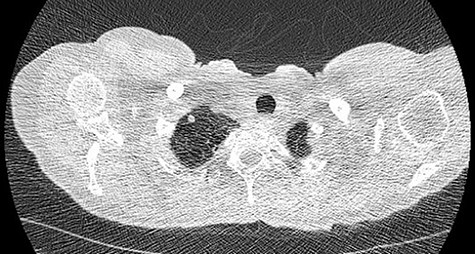

We present a 45 year-old lady who had initially been seen by the respiratory physicians following an admission with acute dyspnoea following influenza infection 1-year prior to her surgery. She had undergone CT scan for abnormal chest radiograph. She had previously worked as a cleaner and was an ex-smoker of 1.5 pack years with no previous asbestos exposure or underlying genetic disease such as tuberous sclerosis or alpha-1 antitrypsin deficiency. She had been followed up in the nodule clinic (a follow-up clinic run by respiratory physicians to monitor solitary pulmonary nodules) with a provisional diagnosis of chronic obstructive pulmonary disease. She had progressive dyspnoea and occasional lower respiratory tract infections treated with courses of antibiotics. Her co-morbidities included previous alcohol dependence and depression. Pre-operative pulmonary function tests demonstrated an FEV1 of 1.53 (53% of predicted), FVC of 2.52 (79% of predicted), diffusing capacity of lungs for carbon monoxide (DLCO) of 5.25 (62% of predicted) and 6 minute walking distance of 414 m. Initial CT imaging findings demonstrated severe, heterogenous right-sided bullous emphysematous changes with a basal predominance and multiple large bullae in the lower lobe (Fig. 1) and a benign inflammatory nodule, which was 7 mm in size in the right upper zone presumably right upper lobe. There was associated hyperinflation causing mediastinal shift to the left with complete right middle lobe collapse and marked compression of the right upper and middle lobes. Due to her increasing symptoms and progressive solitary nodule (Fig. 2) in the right upper zone she was referred for a surgical opinion. Pre-operative echocardiography did not demonstrate any right ventricular dilatation or impairment and no pulmonary hypertension. She was counselled regarding the progressive symptoms, lung function and risk of pneumothoraces and scheduled for right thoracotomy and lower lobectomy. Operative findings were that of large bullous disease affecting the right lower lobe (Fig. 3) with subtotal destruction of the lung parenchyma of the lower lobe. The nodule was present in the apical segment of the lower lobe instead of the upper lobe as expected. Right lower lobectomy was completed un-eventfully and the specimen was sent for histology. The upper and middle lobes were hypoplastic and the post lobectomy space management was a challenge. Post-operatively recovery was complicated by prolonged post-operative air leak managed conservatively and once this eventually settled, the patient was discharged following removal of the chest drain. Histopathological analysis of the right lower lobe specimen demonstrated several large thin-walled cysts with interstitial clusters of spindle cells bordering the cyst and immuno-histological markers (increased expression of VEGF-R3, Podoplanin, LYVE-1 and PROX-1) confirming a diagnosis of LAM. The patient was seen in the thoracic surgery follow-up clinic and a CT abdomen/pelvis was organized to rule out renal angiomyolipomas, associated with LAM in tuberous sclerosis. Referrals were made to the respiratory physicians and the National LAM centre for ongoing management.

CT scan demonstrating heterogeneous bullous emphysema with hyperinflation of the right lung and mediastinal shift.